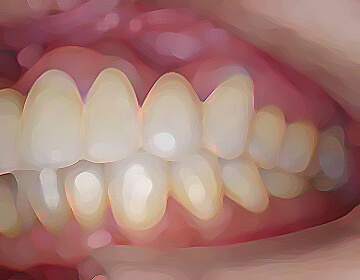

矯正治療では、歯並びを治すだけでなく、噛み合わせの改善によって3次元的顎の位置を修正し、

顎のバランスを整えることで全身のバランスを最良の状態へと導きます。

経過を診ながら、矯正後治療が必要な歯を治療します。

ブラケット除去、リテーナー装着し、経過を確認します。